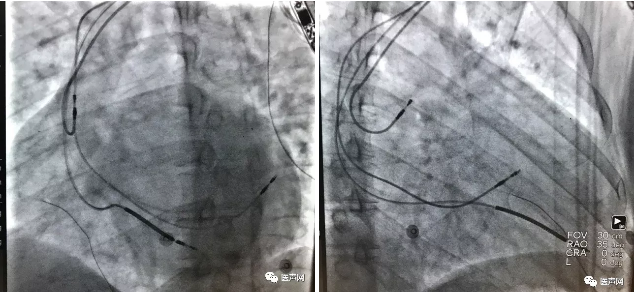

术后程控优化,经AV间期及VV间期调整,对QRS宽度进行比对。

最终确认参数,AV间期190ms,VV间期为左右室同时,QRS时限为110ms。